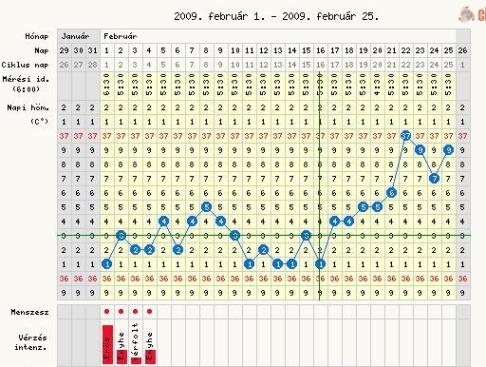

Princzike, szép görbusz!!!